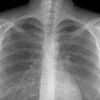

- флюорографічне обстеження населення, починаючи з 15 років;

Відповідь тільки одна: необхідно якомога швидше звернутися до лікаря в поліклініку та негайно зробити флюорографічне або рентгенологічне обстеження. Не намагайтеся займатись самолікуванням, воно не буде ефективним! Не втрачайте дорогоцінний час! Потурбуйтеся про себе та своїх близьких, а лікування на ранній стаді допоможе уникнути небезпечних ускладнень та марних страждань і збільшить шанси на повне видужання.